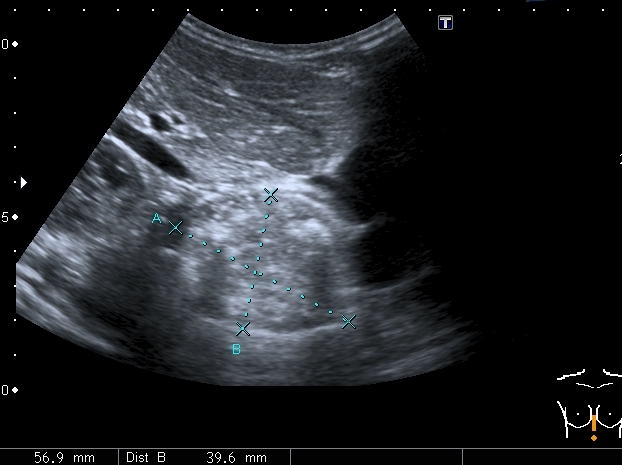

Девочка 4-х лет, жалобы на длительный кашель (оеоло 1-го месяца). В поликлинике выполнена рентгенография органов грудной клетки, выявлены изменения (какие - пока не скажу). Госпитализирована. Направлена на УЗИ сердца. При УЗИ - в самом сердце - патологии не выявлено, но позади него к правому предсердию прилежит полостное образование с акустически неоднородным содержимым.

Анализы крови - не изменены, температуры - нет. Девочка чувствует себя хорошо. Небольшая подсказка: я перешёл с секторального кардиологического датчика на абдоминальный...Serg

Сканы через пищеводное отверстие диафрагмы